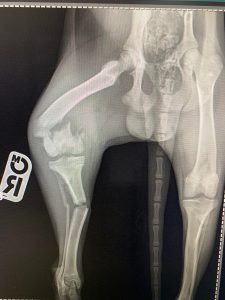

- Liječenje prijeloma kostiju, uključujući intraartikularne frakture

- Hirurške intervencije na zglobovima(artrotomija, artrodeza)

- Korektivne osteotomije za ispravljanje deformiteta